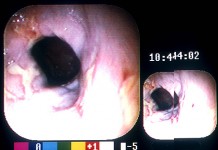

Пищевод Баррета

Синдром Баррета – это замещение эпителия, выстилающего слизистую пищевода, эпителием схожим по строению с тем, который выстилает кишечник. Что такое пищевод Баррета Пищевод Баррета – это...